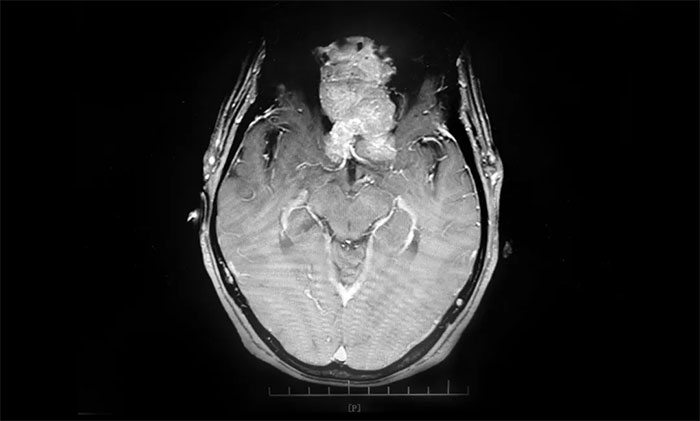

▲ 通過(guò)增強(qiáng)磁共振影像,可見(jiàn)前顱底嗅溝腦膜瘤,體積巨大

頭部增強(qiáng)磁共振影像顯示,患者前顱底嗅溝腦膜瘤體積約6.7*6.4*5.1公分,大如鴨蛋,屬巨大腦膜瘤,瘤體一小部分已經(jīng)延伸侵犯到篩竇內(nèi)。經(jīng)評(píng)估并充分告知手術(shù)風(fēng)險(xiǎn)后,7月9上午,李志強(qiáng)主任為患者實(shí)施巨大腦膜瘤切除手術(shù)。